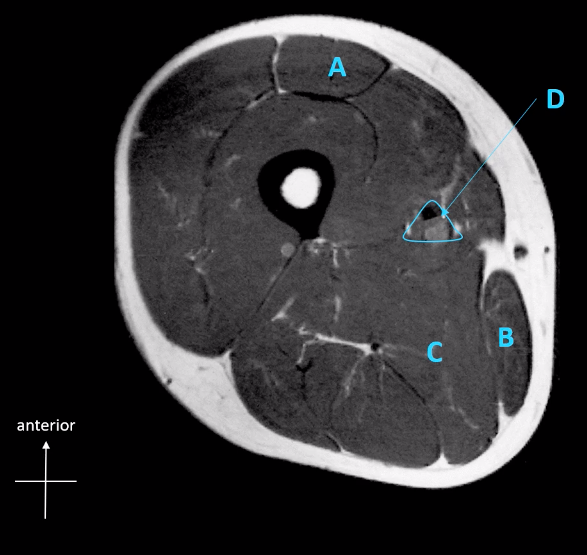

A: Rectus femoris muscle

B: Gracilis muscle

C: Adductor magnus

D: femoral artery / vein